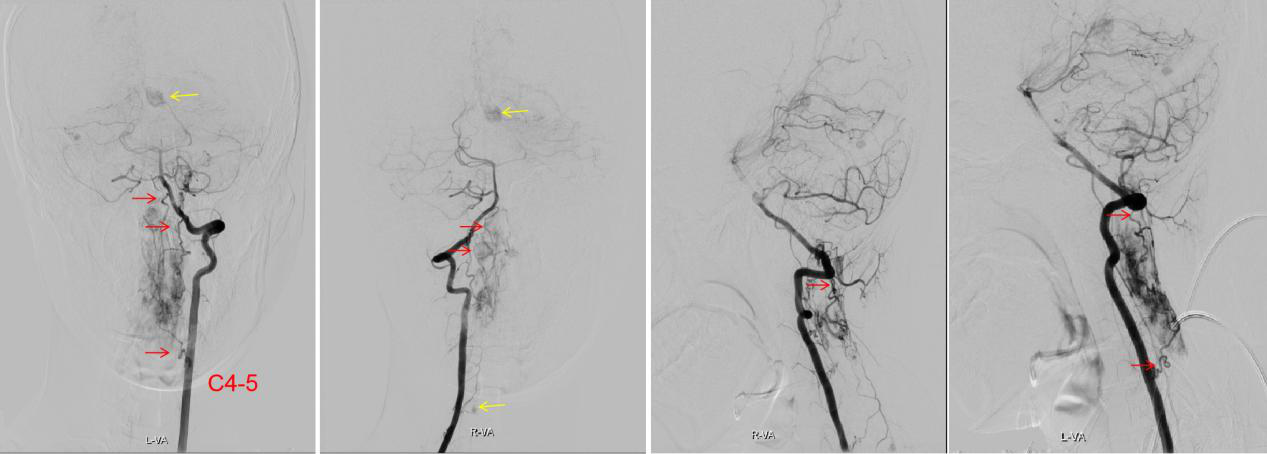

图1 雯雯磁共振发现脑和脊髓上多发的血管母细胞瘤

其实雯雯罹患的是一种常染色体显性遗传病——Von Hippel-Lindau综合征,这种病会造成中枢神经系统的多发血管母细胞瘤,同时还常合并肾脏或胰腺囊肿、嗜铬细胞瘤、肾癌以及外皮囊腺瘤等疾病,目前主要以手术治疗为主。对于有家族遗传史的病人,妊娠期需要做基因筛查,优生优育。考虑到雯雯目前病情紧急,已经出现四肢瘫痪和呼吸困难,住院后王贵怀教授团队紧急讨论制定了手术方案,先期处理延颈髓巨大血管母细胞瘤,术前行全脑和脊髓血管造影,明确肿瘤血供,彻底切除病灶。